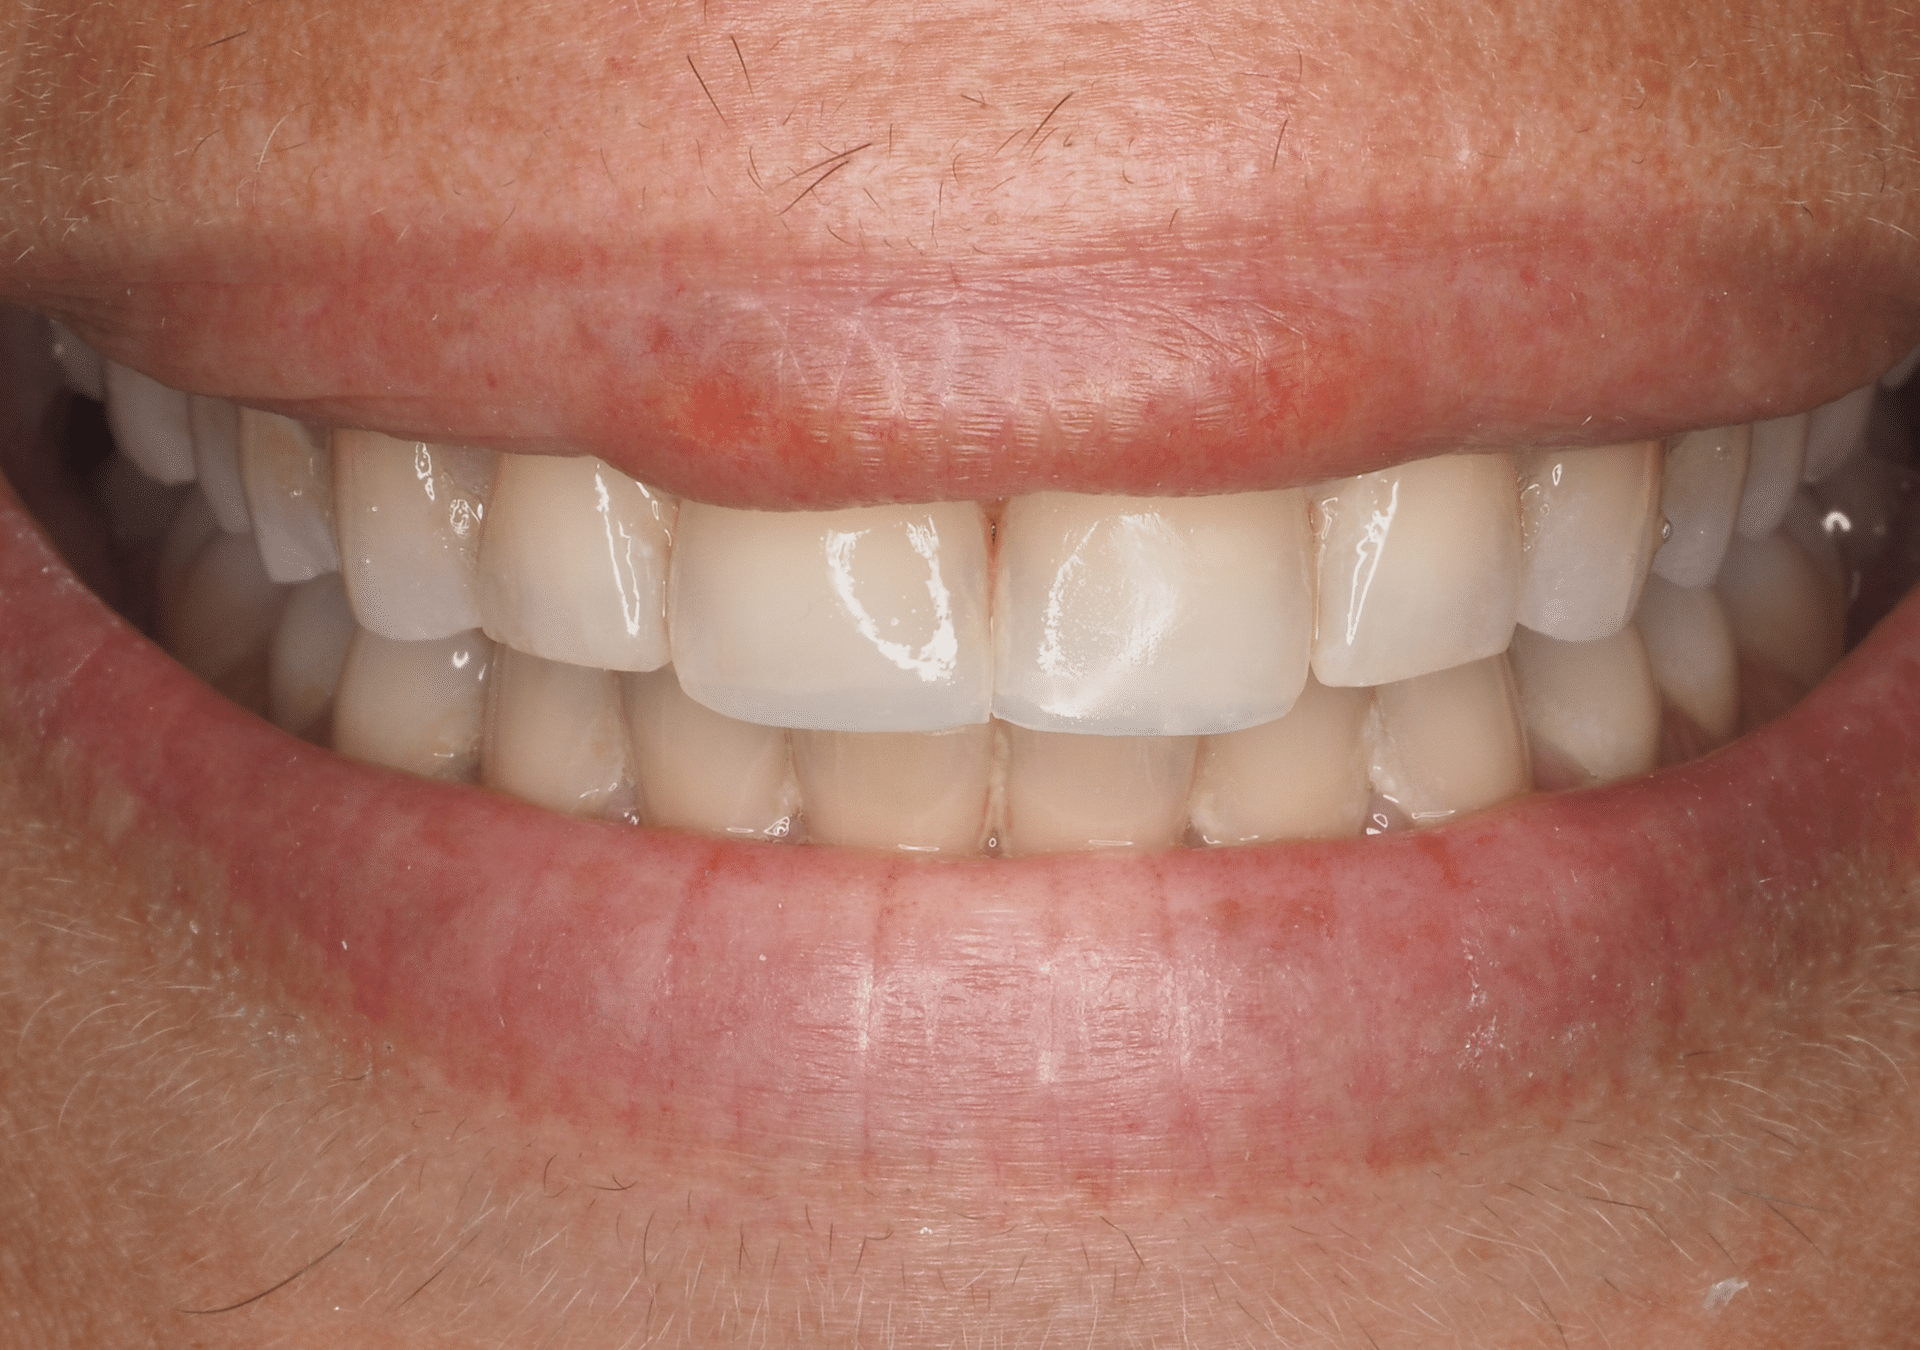

Caso 2

Rehabilitación con cerámica feldespática de paciente con amelogénesis imperfecta (esmalte defectuoso), eliminación de tinciones y protección superficies.